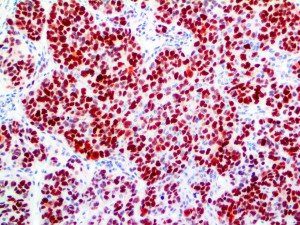

The first cytokines released are interleukin 1β (IL-1β) and tumor necrosis factor-α (TNF-α), which attract a variety of circulating white blood cells (WBCs) to the infection site, including neutrophils, monocytes, macrophages, and natural killer (NK) cells. This response, along with the antipathogenic chemicals released by these cells (i.e., complement), comprise the innate immune response. These cells directly attack the invading pathogen and also release additional cytokines, chief among them interleukin-1 and 6 (IL-6). IL-6 is essential for invoking the adaptive immune response, which calls T-cells, B-cells, and T helper (Th) cells to the infection site. IL-6 also stimulates further recruitment, proliferation and activation of macrophages.

It is the ICU physician who is most likely to witness one of the deadliest manifestations of the abnormal immunological response, the cytokine storm syndrome (CSS). This response is also referred to by some as the cytokine release syndrome (CRS). CSS is characterized by continuous activation and expansion of macrophage and lymphocyte populations, which secrete large amounts of cytokines, causing the cytokine storm. This massive cytokine release is akin to hemophagocytic lymphohistiocytosis (HLH) disease, a syndrome characterized by initial unchecked and persistent activation of cytotoxic T lymphocytes and NK cells.